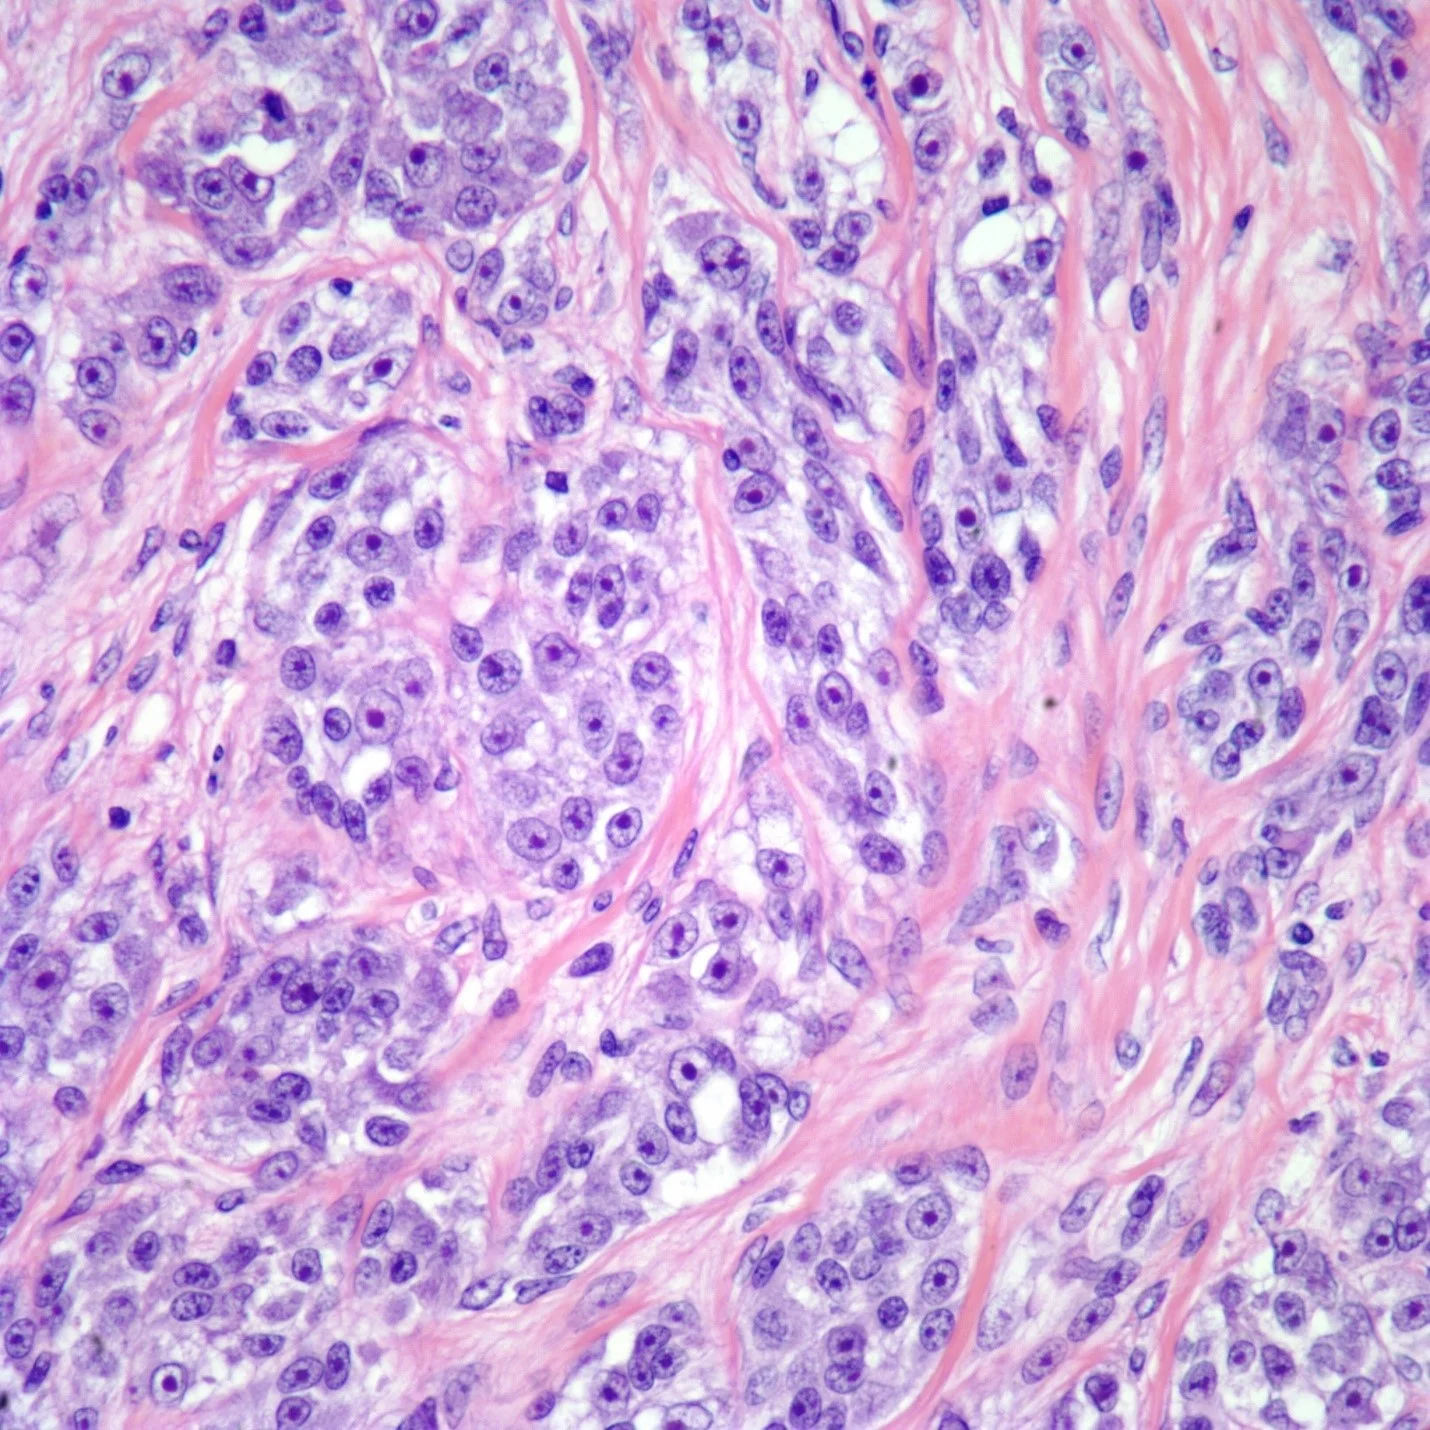

- سارکوم سینوویال (Synovial sarcoma) تومور بدخیم بافت اطراف مفاصل است. شایع ترین مکانها عبارتند از: ران، زانو، مچ پا و شانه. این تومور در کودکان و بزرگسالان جوان شایع تر است اما ممکن است در افراد مسن نیز رخ دهد.